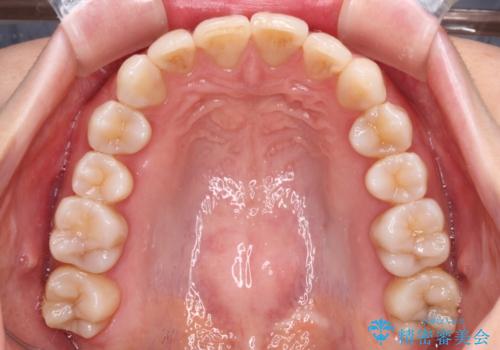

前歯の突出感とデコボコをインビザライン矯正で改善

- 上下前歯の突出感とデコボコを気にして来院された患者様です。

インビザラインによる上下歯列の側方拡大と後方移動、IPR(歯と歯の間を削る)にるスペースの獲得により歯列を整えることとしました。

骨格的な左右差があったため、上下の正中を合わせることができませんでした。

骨格の差は改善できないため、奥歯の咬み合わせに物足りなさを感じましたが、奥歯の咬み合わせによる不自由はなく、口元の突出感も改善することができました。